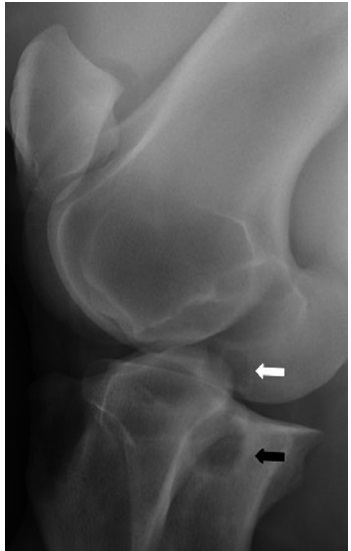

Fig 2: Caudolateral-craniomedial 45° radiographic projection of

the stifle region revealing a medial femoral condyle subchondral

bone cyst (white arrow) and an opposing subchondral bone cyst

(black arrow) in the medial tibial plateau. EVE Bonilla Equine bone cysts: What do we know about them and their